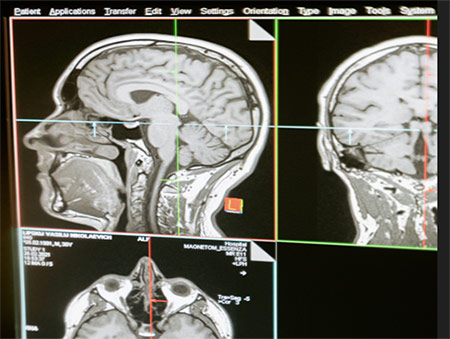

1. Uecker, M., Lai, P., Murphy, M. J., Virtue, P., Elad, M., Pauly, J. M., Vasanawala, S. S. and Lustig, M. (2014), ESPIRiT—an eigenvalue approach to autocalibrating parallel MRI: Where SENSE meets GRAPPA. Magn Reson Med, 71: 990–1001. doi: 10.1002/mrm.24751

Combined parallel imaging compressed sensing reconstruction of an abdomen using l1-ESPIRiT as implemented in the BART toolbox. The scan was accelerated seven-fold using variable-density Poisson-disc sampling.

This article bridges the gap between the two main approaches for parallel imaging (SENSE and GRAPPA) allowing the reconstruction of images from undersampled multicoil data. SENSE explicitly uses coil sensitivities, and GRAPPA makes use of learned correlations in k-space. In this work, Martin Uecker, Peng Lai and colleagues present a new autocalibration technique combining the extended reconstruction of SENSE with GRAPPA-like robustness to errors. A matlab demo, implementation, and reproduction of the results in the paper can be found here.